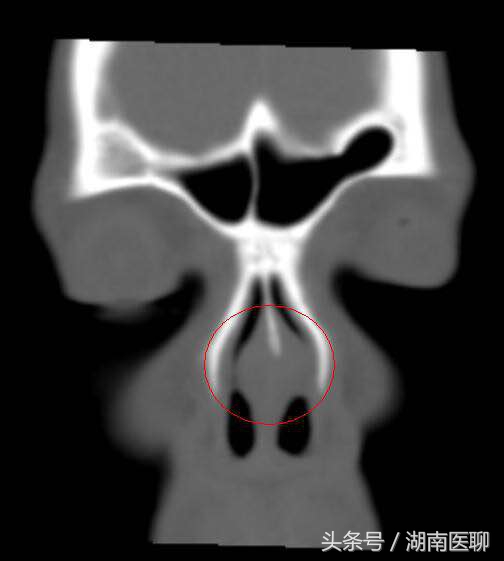

【CT片上可以看到脓肿的鼻中隔(红圈内)】

5天后,雯雯感觉鼻子疼痛难忍,来到湖南省人民医院耳鼻咽喉头颈外科肖旭平教授处就诊,被确诊为“鼻中隔脓肿”,需住院治疗。经过几天的抗炎、补液治疗后,雯雯的病情明显好转,正在康复中。